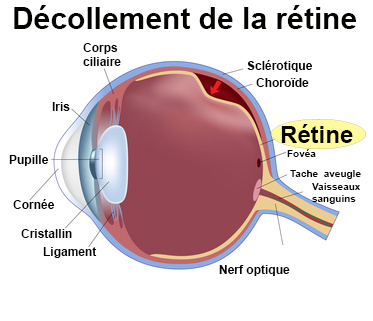

blog.ophtalmique.chDéfinition | Décollement De La Rétine | Futura Santé

blog.ophtalmique.chDéfinition | Décollement De La Rétine | Futura Santé

www.coss-ophtalmologie.parisDécollement De La Rétine : Symptômes, Traitement, Définition

www.coss-ophtalmologie.parisDécollement De La Rétine : Symptômes, Traitement, Définition